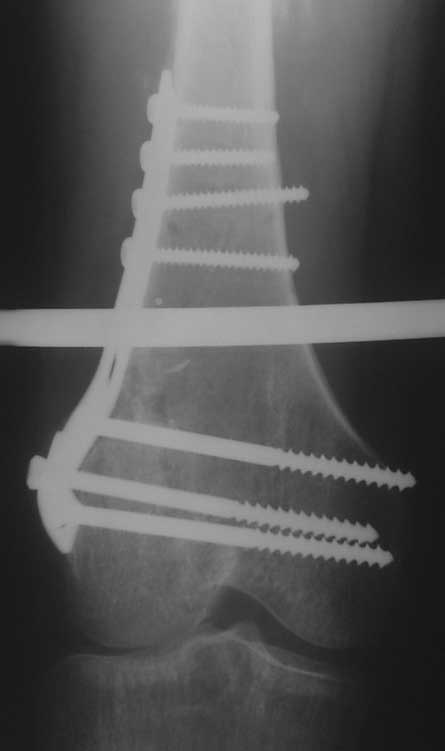

Уважаемые коллеги, помогите пожалуйста с тактикой лечения. Больная 43 лет, подвернув правую ногу, получила простой (А2) перелом правого бедра в с\3, м\у установленными ранее пластинами. В течении 4 недель лечится методом скелетного вытяжения.В анамнезе: в июне 2011г. получила перелом наружного мыщелка правого бедра на фоне консолидированного в порочном варусном положении перелома вертельной зоны (со слов травма 5 лет назад - лечилась консервативно), сопровождающимся укорочением 5 см. В одну операционную сессию выполнен остеосинтез перелома мыщелка бедра Т-образной пластиной и с целью коррекции укорочения выполнена вальгизирующая межвертельная остеотомия с фиксацией клинковой пластиной.На наш взгляд, наиболее простым является накостный остеосинтез диафизарного перелома по передней поверхности бедра, но смущает необходимость образования в последующем дополнительного кожного рубца. Пожалуйста, может быть у Вас есть другие мнения. Зарание благодарен. С уважением А.Гринь. ОКБ №2 г.Тюмень.

М\У пластины - наверное слово между пластинами, зачем такие сокращения не понятно. Хотя боковых рентгенограмм нет, можно предполагать что мыщелки бедра с июня вероятно в стадии активноой консолидации. В связи с чем в большей мере согласен с Челноковым А.Н. и удалил бы старые фиксаторы перейдя к блокироанному бедренному гвоздю с дистальной полиаксиальной фиксацией. Если есть какие-нибудь осложняющие моменты то аппарат Илизарова более выгоден пациенту, чем третья пластина.

Из возможных операций: я бы предложил провести ретроградную фиксацию бедра после удаления дистальной пластины. При отсутствии полного сращения перелома можно установить пару шурупов спереди и сзади гвоздя, или можно оставить укороченный вариант пластины.

Гвоздь подвести под вертел, и оставить проксимальный винт, а остальные шурупы могут быть через один кортекс. Идеально установить "стоппер", который укоротит клинок и латерализует диафиз. Создаст компрессию!

Из бокового "субвастусного" доступа можно уложить пластину спереди, но тогда надо подождать с нагрузкой. Провокационный антеградный вариант технически сложен, но тогда теряется преимущества сколжения клинка в шейке, и потом клинок не разрушает, как остальные дивайсы, костную структуру в головке.